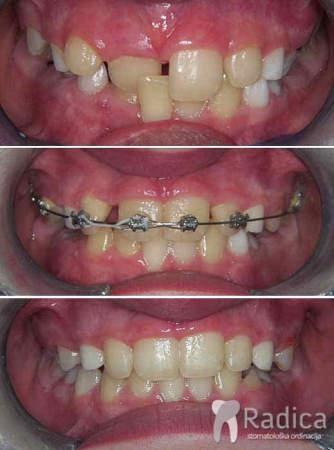

Duboki zagriz i perzistentni gornji desni mliječni očnjak, impakcija desnog trajnog gornjeg očnjaka i genetski nedostatak gornjih lateralnih sjekutića („dvojki“), na ćije mjesto su pomaknuti očnjaci i preoblikovani: